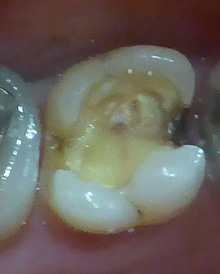

40代の女性 です。

写真 真ん中の歯の一部に

穴が開いていますが、

痛みはないそうです。